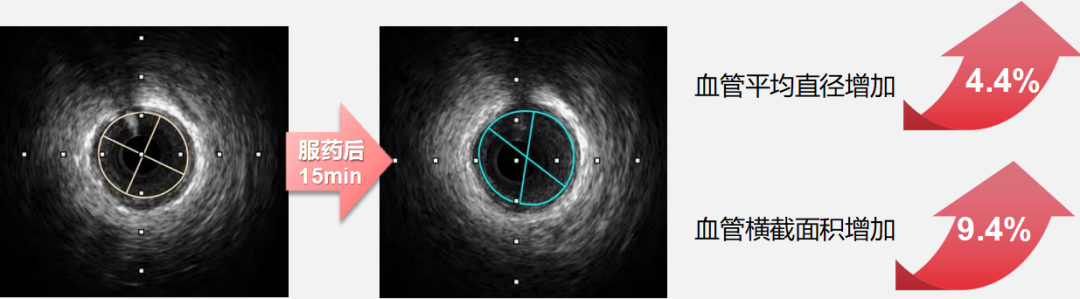

●而速效救心丸展現(xiàn)出 “精準(zhǔn)化” 的血管調(diào)控特征:對直徑 2.00-2.75mm 的細(xì)小冠狀動脈擴(kuò)張作用更突出,服藥后15 分鐘該直徑區(qū)間血管橫截面積面積擴(kuò)張百分比最高可達(dá) 8.58%(如下圖),且擴(kuò)張過程中患者血壓、心率等血流動力學(xué)指標(biāo)無顯著波動。